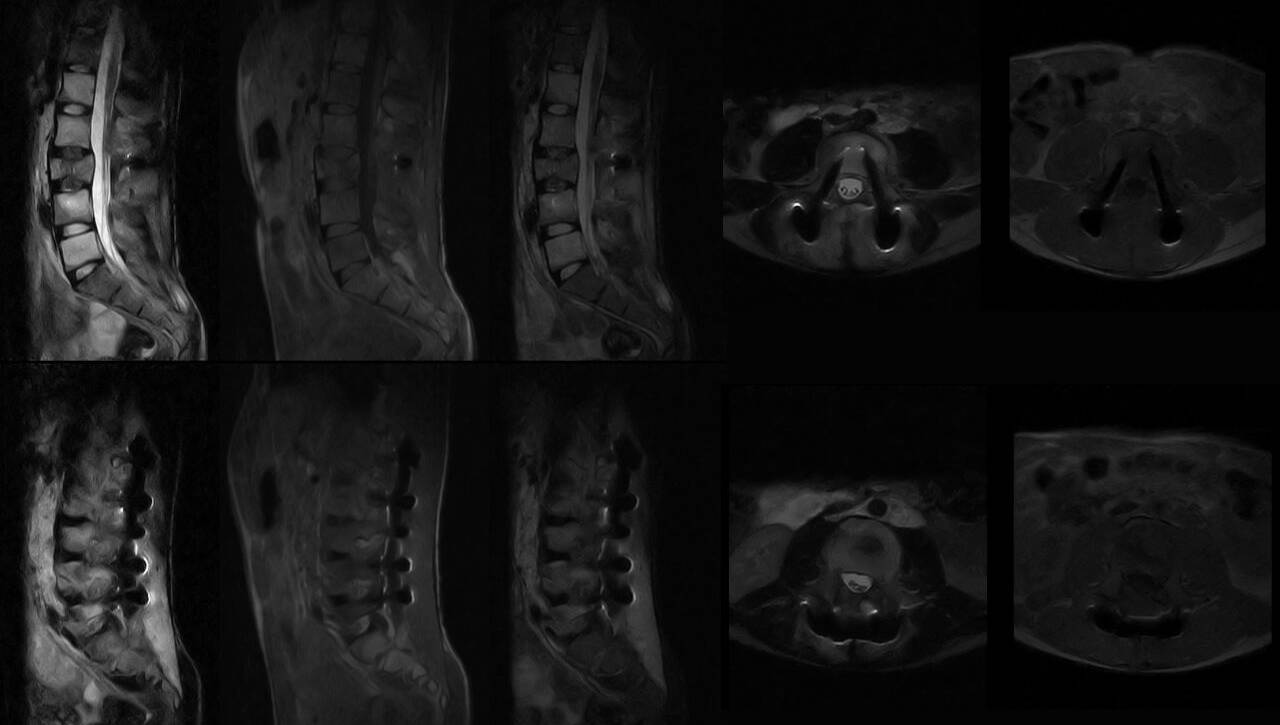

ressonância magnética (RM) é uma técnica de imagem médica amplamente utilizada para obter imagens detalhadas de órgãos e tecidos do corpo, sem o uso de radiação ionizante. Contudo, quando se trata de grávidas, a realização desse exame requer uma atenção especial.

Desafios da ressonância magnética tradicional e implantes metálicos

A ressonância magnética tradicional utiliza um campo magnético de alta potência para produzir imagens detalhadas do corpo humano. No entanto, quando há presença de implantes metálicos, esses dispositivos podem causar distorções significativas nas imagens, tornando-as inutilizáveis para diagnóstico médico. Essa interferência ocorre porque os metais são condutores…